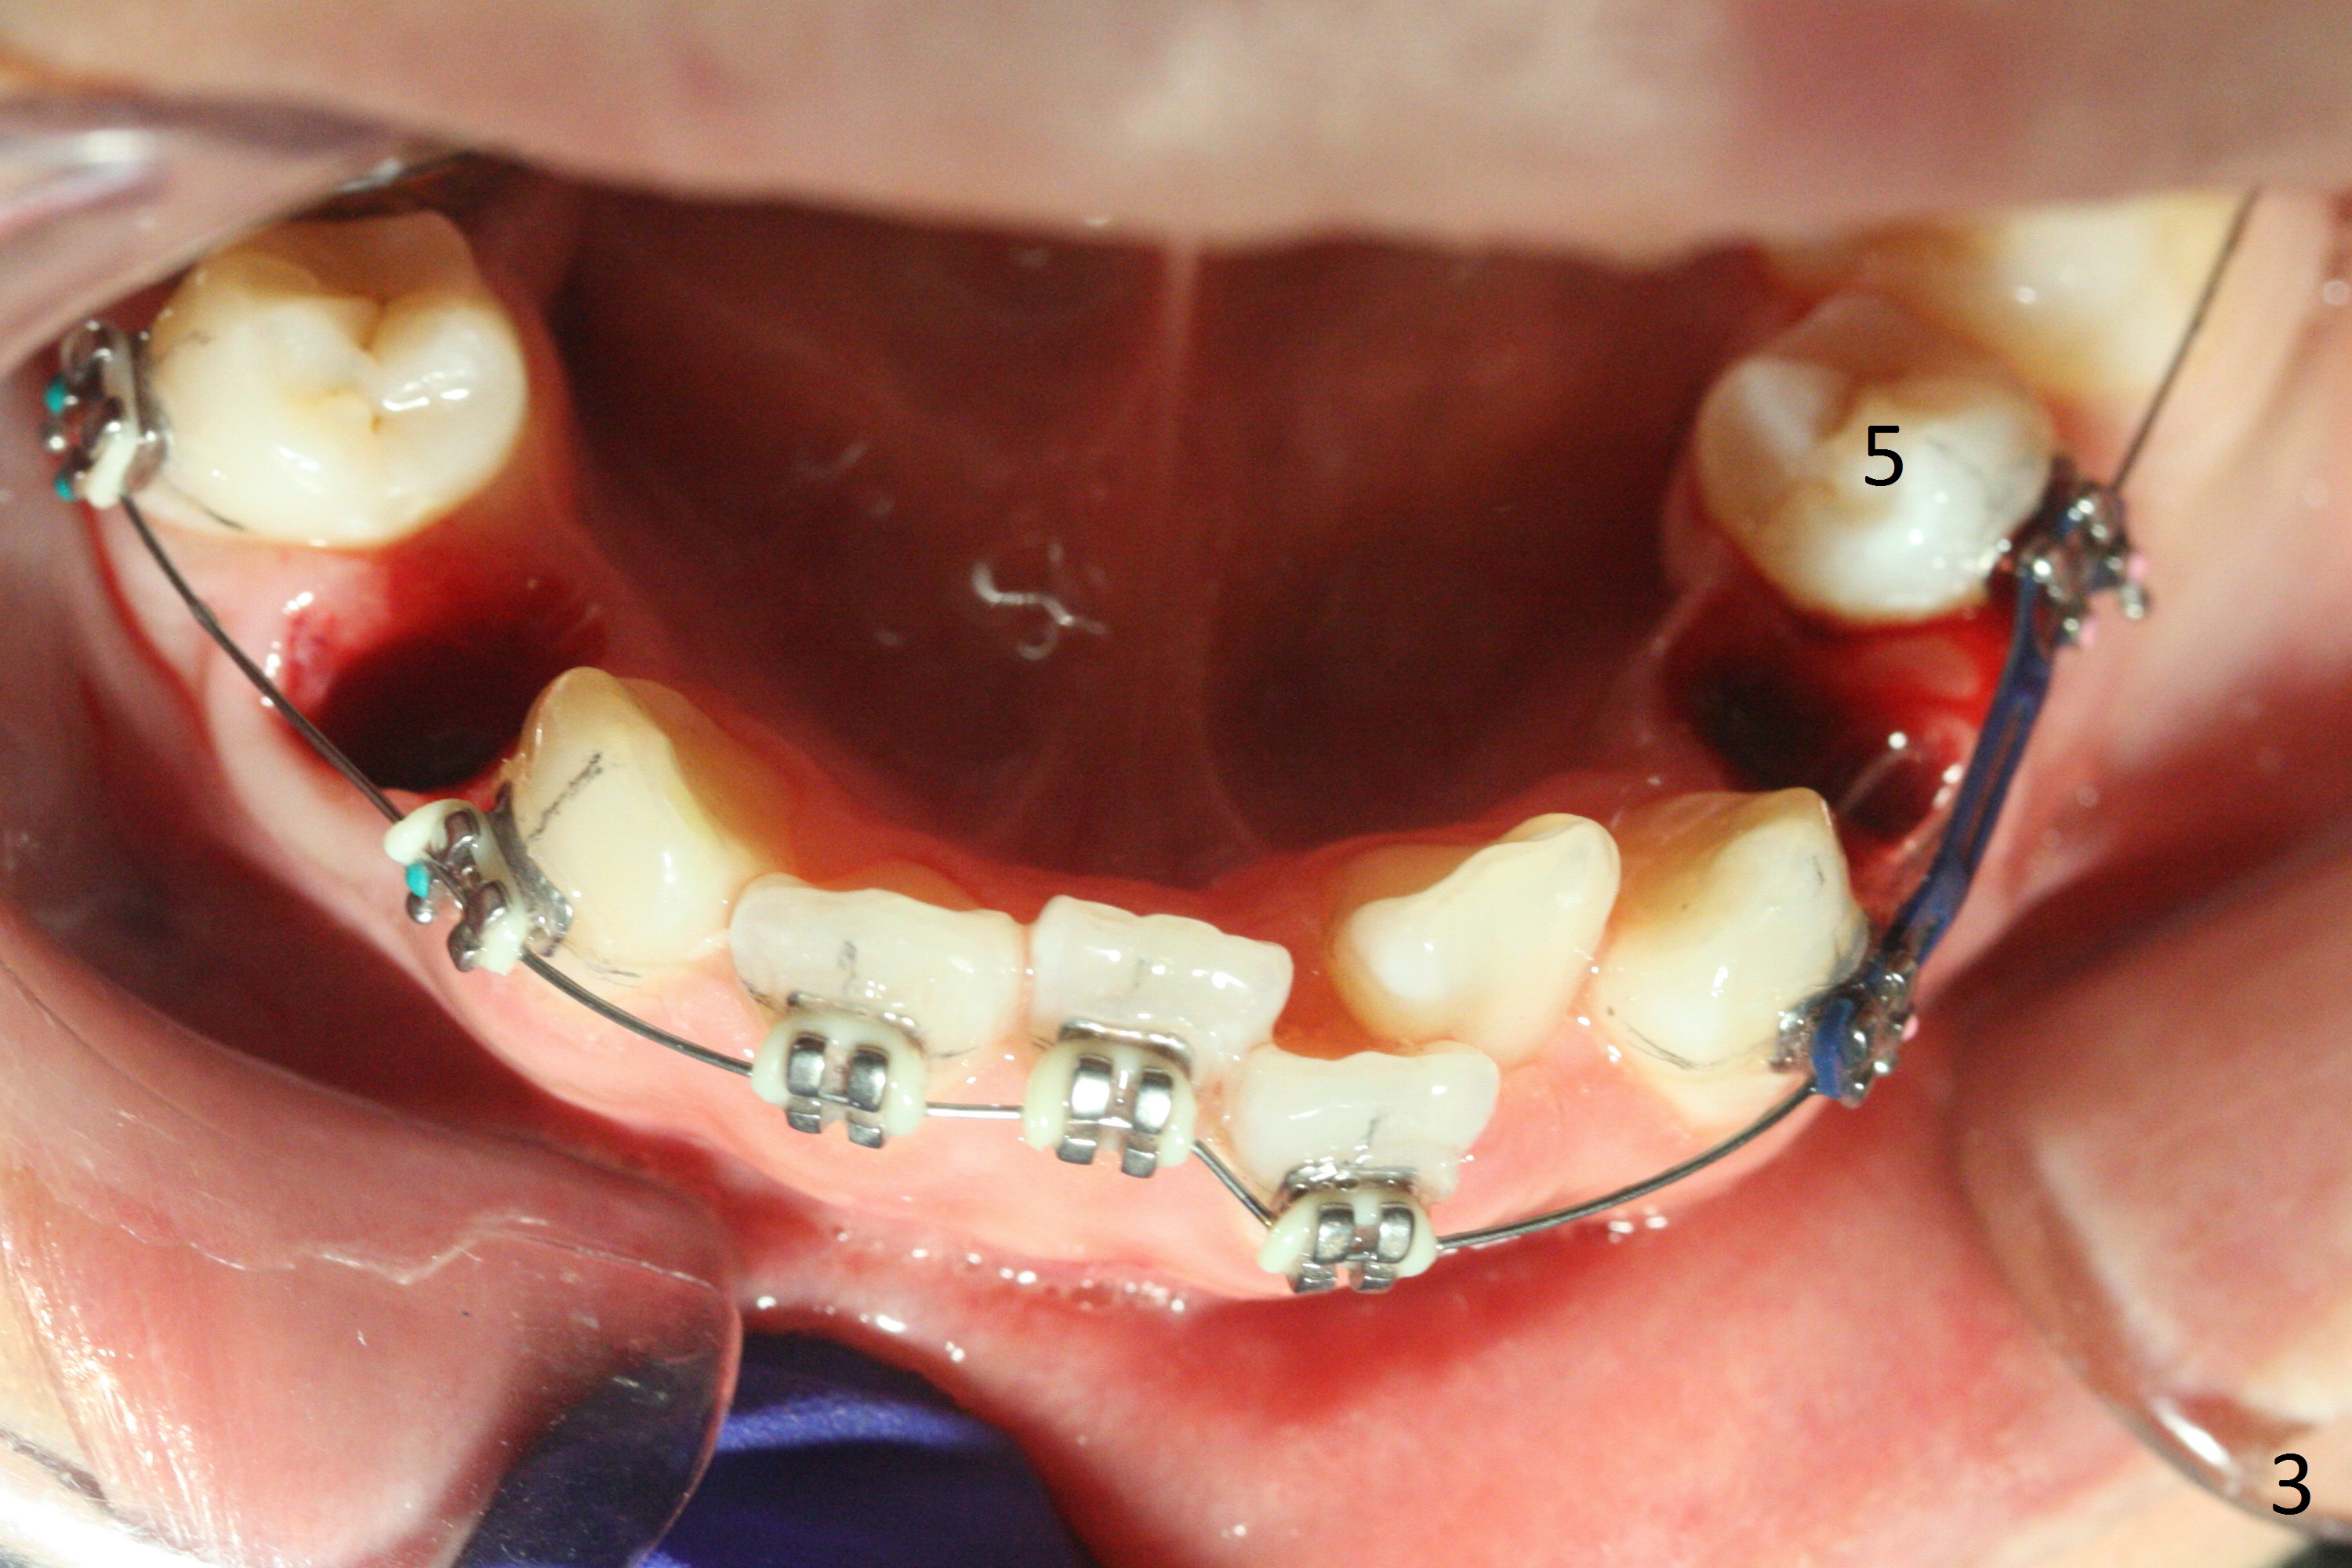

For the lower left quadrant, a band is placed at 7, but not at 6, since the space between 5 and 6 is not enough. A new separator is placed between 6 and 7, while power chains are placed between 3 and 5 (Fig.3). The patient will return for banding at 6 next week.